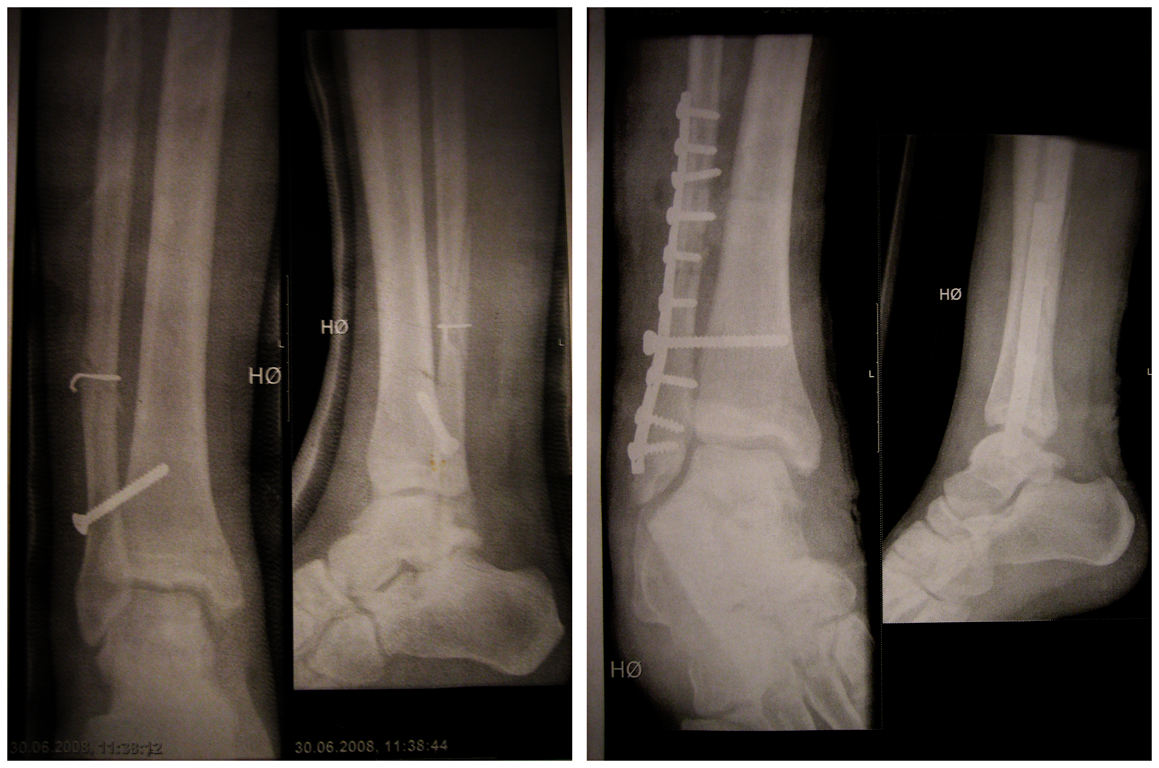

Jeg så røntgenbildene etter operasjonen i Polen:post-166839-1239910089_thumb.png

Fra bloggen: "ULIKE METODER: Til venstre er en ankelbrudd-operasjon etter polsk standard, og til høyre en norsk. Bedøm selv."

Så ja, jeg ville studert i Norge, hvis jeg var dere...

ScapulaA: Vet du hvorfor det er en skrue fra fibula til tibia? :)

ScapulaA: Vet du hvorfor er det en skrue fra fibula til tibia? :)

Fordi det er en ustabil fraktur og skruen er med på å immobilisere ankelleddet? Tipper det er noen ligamenter som er revet av, og at skruer hjelper til å stabilisere ankelleddet i deres fravær. Man trenger ikke være ortoped for å se at den polske versjonen har feilstilling (som kan gi senfølger) og er mindre stabil med tanke på skruer og plater. Jeg håper at årsaken til den operasjonen har med penger/ressurser i Polen å gjøre, og ikke manglende kunnskap :)